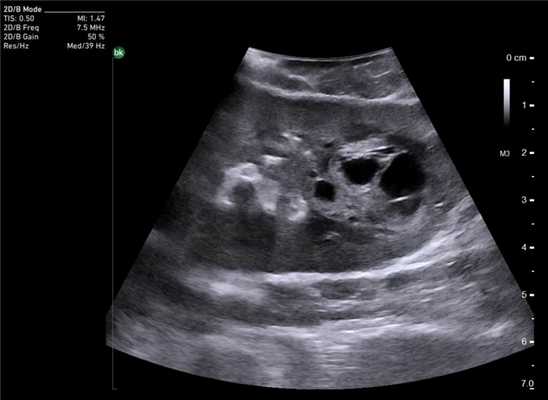

Особенностью проведения интраоперационного ультразвукового исследования у пациентов с первичным поражением печени является то, что гепатоцеллюлярный рак часто развивается на фоне цирроза печени. Следовательно, если опухоль локализуется в толще паренхимы, а так же имеет не большие размеры, пальпаторно определить ее границы крайне затруднительно. Таким образом, задачи установленные перед интраоперационной ультразвуковой томографией были несколько иными, а именно: определение границ опухоли, разметка зоны резекции, определение связи с магистральными сосудами (рис. 2 а,б).

Рис. 2. Метастатические очаги (стрелки) в печени на фоне цирроза.